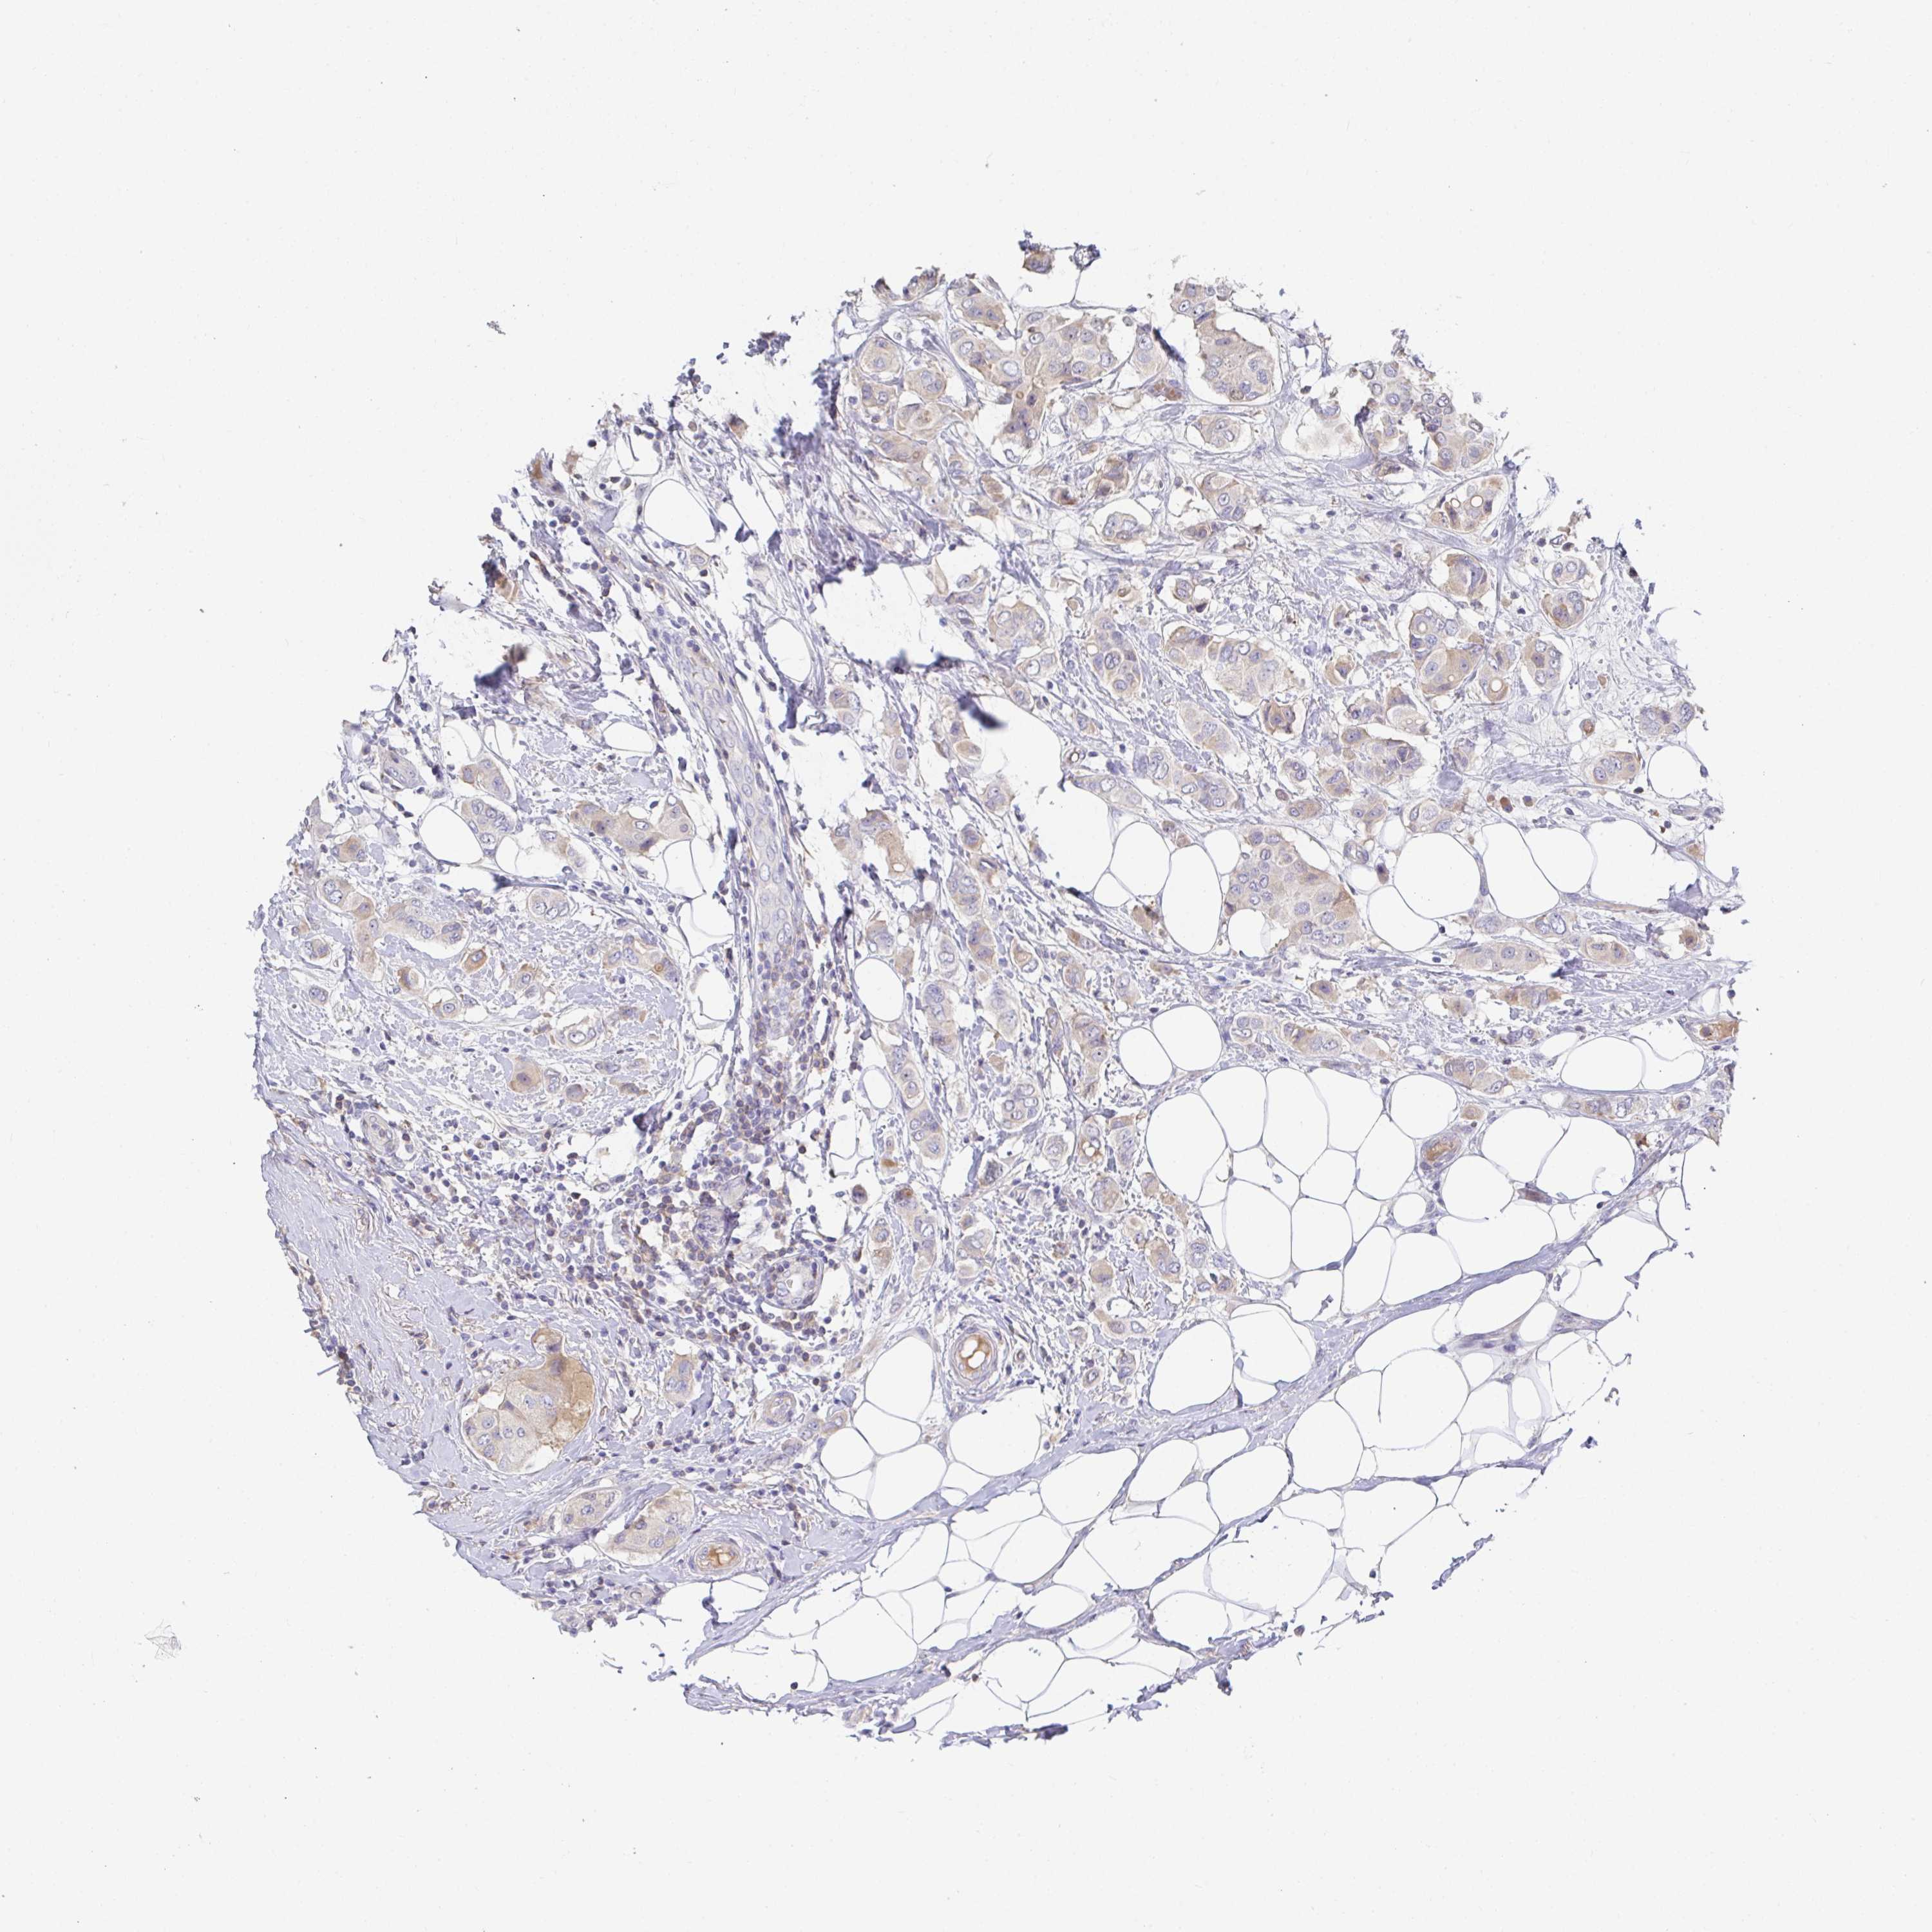

CANCER BREAST CANCER Show tissue menu

BRCA TCGA BRCA VALIDATION PROTEIN EXPRESSION